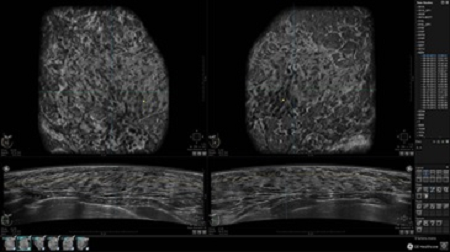

GE INVENIA ABUS – это современный УЗИ аппарат, который создан для точной и эффективной диагностики сканирования с высокой плотностью молочных желез. Выявляемость патологий раковых и предраковых стадий заболевания составляет 55%, что в конечном счете позволяет ставить врачу точные и своевременные диагнозы. Традиционные методы использования маммографии не показывают такой выявляемости, ограничиваясь лишь 3-38%.

УЗИ-аппарат GE INVENIA ABUS позволяет проводить максимально операторонезависимые процедуры, что значительно снижает риск неправильной постановки диагноза и сопутствующие издержки на обработку информации. Система готовит отчет в течение 3-х минут после сканирования, это безусловное преимущество по сравнению с обычным УЗИ сканером.

• Одновременный просмотр двух изображений для сопоставления в коронарной плоскости

• Многооконный просмотр: 4 - 12 изображений